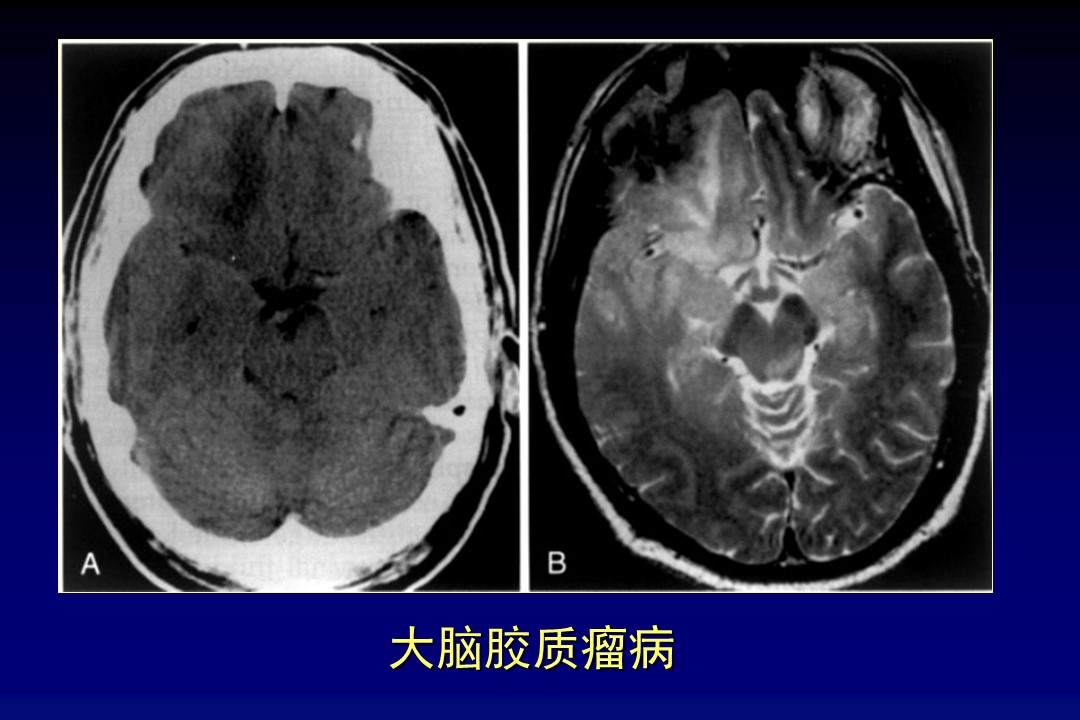

“脑瘤疑难病例影像学诊断分析” 的相关文章